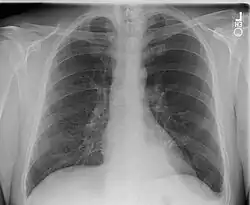

Wada przebiegająca bezobjawowo, bez połączenia z oskrzelem, może być wykryta przypadkowo na zdjęciu przeglądowym klatki piersiowej jako okrągława masa o wysyceniu typowym dla tkanek miękkich, najczęściej zlokalizowana nad przeponą w dolno-tylnej części lewego płuca. Obraz radiologiczny objawowej sekwestracji płucnej naśladuje zmiany torbielowate, jamiste lub marskie. Aortografia pozwala ocenić zaopatrzenie zmiany w naczynia tętnicze.